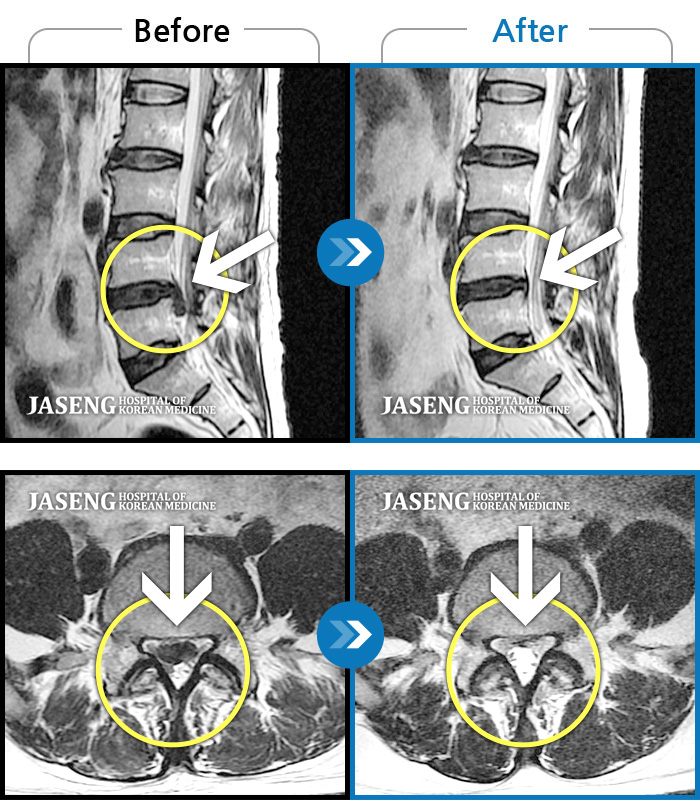

허리디스크

일산 · 김태용 원장

허리 및 양쪽 골반에 심한통증으로 일주일간 거동이 불가능 했으며 우측 하지로 방사통이 심한 상태

촬영시기

2020.05.08 ~ 2020.12.22

2020.12.24

조회수 74